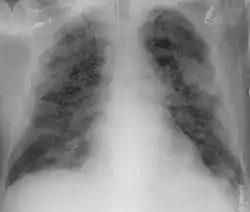

Imaging

Chest CT scans may be helpful to diagnose COVID-19 in individuals with a high clinical suspicion of infection but are not recommended for routine screening.[93][105] Bilateral multilobar ground-glass opacities with a peripheral, asymmetric, and posterior distribution are common in early infection.[93][106] Subpleural dominance, crazy paving (lobular septal thickening with variable alveolar filling), and consolidation may appear as the disease progresses.[93][107] Characteristic imaging features on chest radiographs and computed tomography (CT) of people who are symptomatic include asymmetric peripheral ground-glass opacities without pleural effusions.[108]

Many groups have created COVID-19 datasets that include imagery such as the Italian Radiological Society which has compiled an international online database of imaging findings for confirmed cases.[109] Due to overlap with other infections such as adenovirus, imaging without confirmation by rRT-PCR is of limited specificity in identifying COVID-19.[108] A large study in China compared chest CT results to PCR and demonstrated that though imaging is less specific for the infection, it is faster and more sensitive.[92]

Chest X-ray showing COVID-19 pneumonia